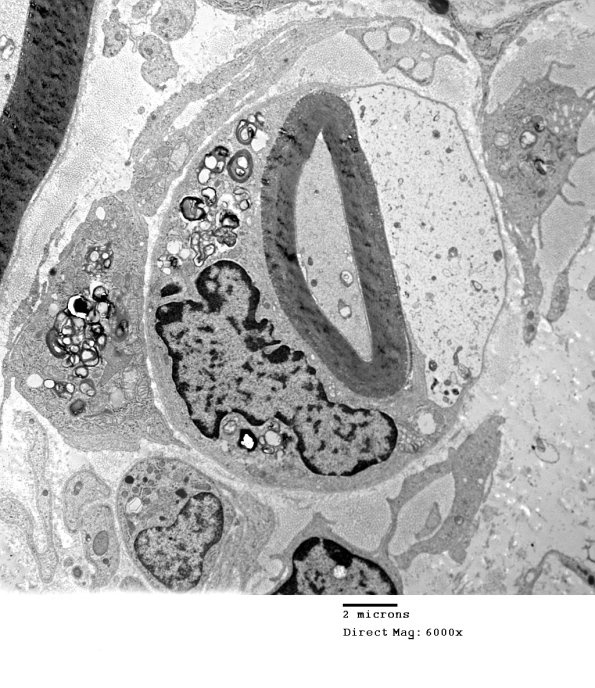

1D7A,B The pale Schwann cell cytoplasm may be a feature of this case. Notice the multiple macrophage processes peeling off the myelin (arrow, 1D7B)